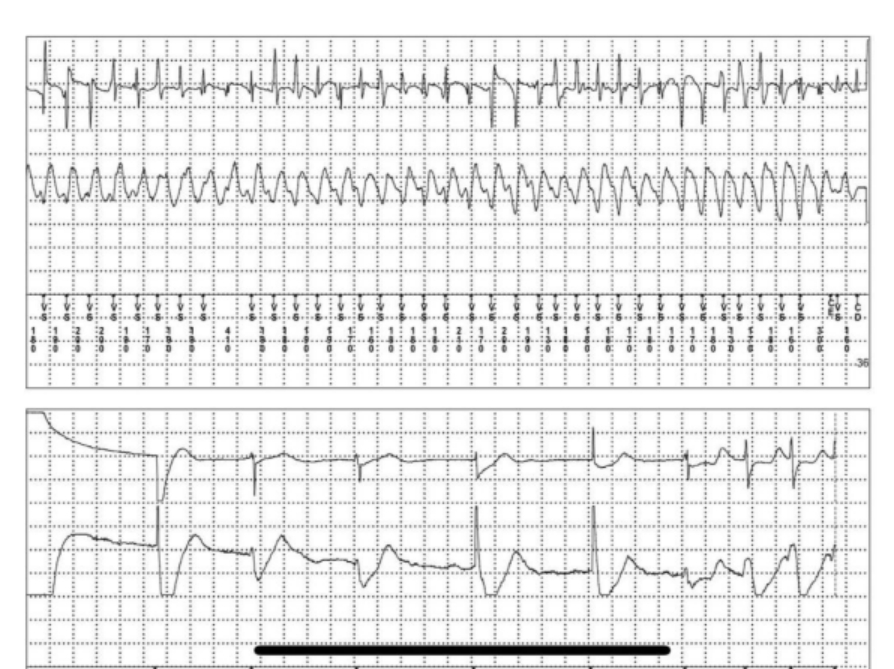

(图为患者发作恶性心律失常及放电时的心电图)